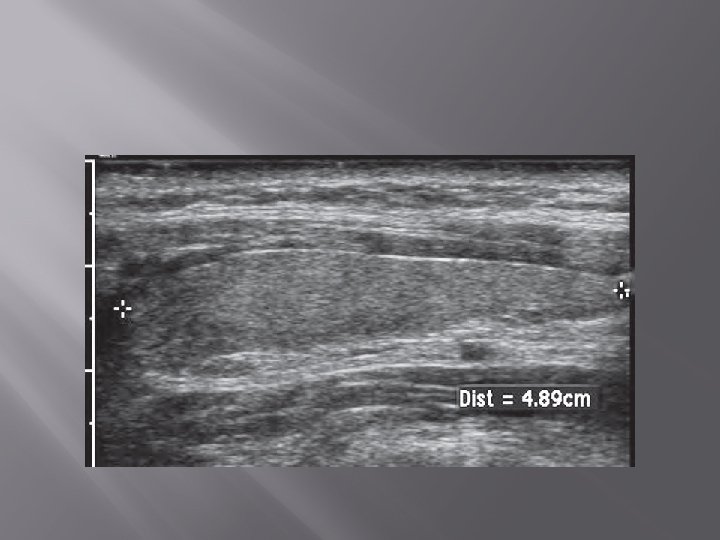

1. Ultrasonography (USG) � � Gray scale, color Doppler Transducer : linear frekuensi tinggi (7. 5 -15. 0 MHz)

� � Ukuran normal kelenjar thyroid orang dewasa Indonesia : 4 -4, 8 cm x 1, 0 -1, 8 cm x 0, 8 -1, 6 cm. Berat normal : neonatus 2 -3 gram. Orang dewasa 18 -20 gram

� Normal thyroid parenchyma has a homogeneous, medium-level to high-level echogenicity that makes detection of focal cystic or hypoechoic thyroid lesions relatively easy in most cases.